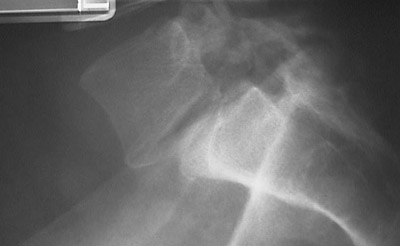

This radiograph of the spine demonstrates spondylolisthesis with slippage of the L5 vertebral body anterior to the S1 body. This can lead to spinal cord nerve root injury with slippage of the intervertebral disk.